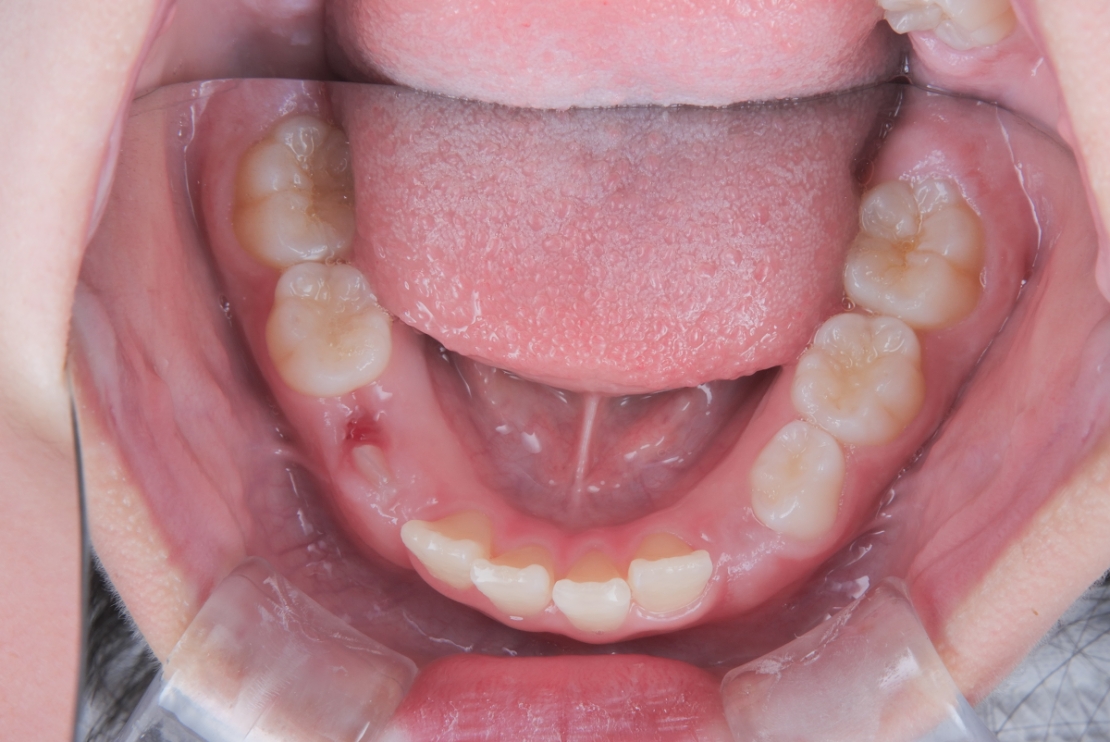

AFTER

治療は、マウスピース矯正インビザライン・ファーストにて矯正治療を行い、成長を活かしながら歯列を整えていきました。治療期間はわずか11ヶ月で完了し、ガタつきと歯の傾きは改善しています。

治療終了時に「痛みはどうだった?大変じゃなかった?」とご本人にお聞きしたところ、「全然大丈夫だった!」と笑顔で答えてくださいました。無理なく前向きに取り組んでいただけたことが印象的な症例です。